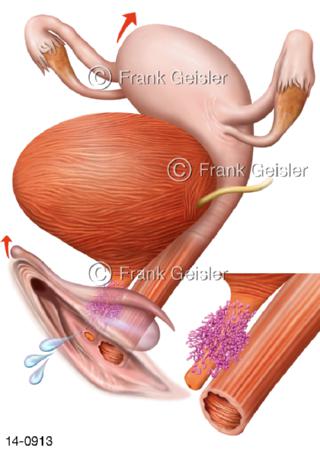

Bildergalerie Urogenitalsystem

Bilder zum Urogenitalsystem mit Urogenitalorgane, Urogenitaltrakt, zum Harn- und Geschlechtsapparat, Harnorgane und Geschlechtsorgane, Organe der Harnwege und der Fortpflanzung, Harnorgane und Geschlechtsorgane im männlichen und weiblichen Urogenitalsystem